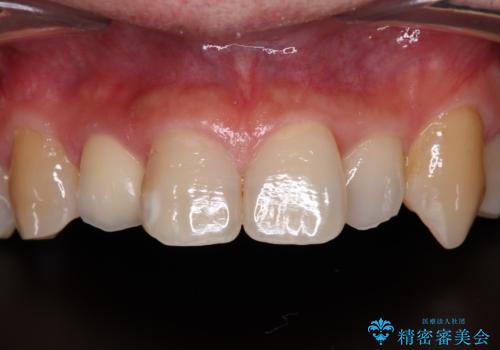

- 内側に倒れている前歯が擦れてしみるとのことで来院された患者様です。

削れていた部分は詰め物が入っていましたが、縁の部分がしみているようで、変色も目立っていたため、オールセラミッククラウンにて補綴治療を行うこととしました。

内側に倒れているため、下顎と強く干渉することが懸念されましたが、無理のない咬み合わせで、形態も左右対称に近い状態で仕上げることができました。